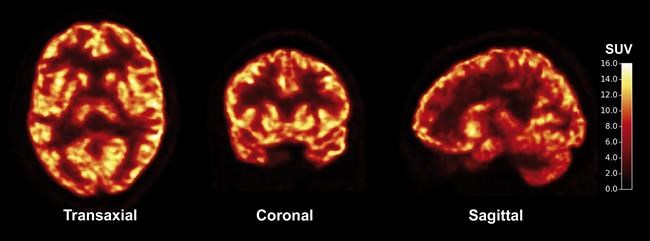

WASHINGTON – The brain’s nerve cells communicate by firing messages to each other through junctions called synapses, and problems with those connections are linked to disorders like Alzheimer’s and epilepsy. Now Yale University researchers have developed a way to picture synapses in living brains.

The technique reported Wednesday, using PET scans, is highly experimental but it raises the possibility of one day monitoring synapse function in some common diseases.

To find a non-invasive approach, the Yale-led team developed a radioactive compound, called a tracer, that is injected into the body and binds with a particular protein that is found in the brain’s synapses. The idea: During a PET scan, those synapses appear lit up against dark, synapse-free areas of the brain.

The research team then mapped the density of synapses in the brains of 10 healthy volunteers and three patients with a form of epilepsy. Compared to the healthy brains, the technique revealed lost synapses in the epilepsy-affected regions of those patients’ brains, the researchers reported Wednesday in the journal Science Translational Medicine.